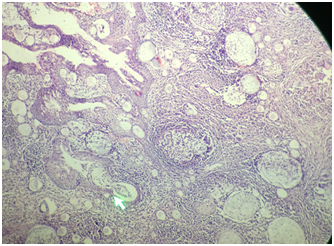

48 year old male coast guard personnel, a known case of Primary Hypertension and Type II Diabetes Mellitus, presented to this centre with Left nasal mass and bleeding from Left nostril of 04 months duration. There was history of similar complaints for the past 23 years. History of bathing in pond in his village which is in Southern part of India since his childhood. No history of rhinorrhoea /excessive sneezing/trauma to nose. Patient was diagnosed as Rhinosporidiosis and underwent excision of the mass thrice, in 1994, 2006 and 2017. On evaluation, there was a red friable mass filling Left nasal cavity, with spores seen on the surface and bleeds on touch (Figure 1). Computed Tomography of Paranasal sinuses (PNS)–shows Left nasal cavity filled with soft tissue on the anterior aspect, absent middle and inferior turbinate (Figure 2). He underwent Nasal Endoscopic Excision (Microdebrider & CO2 laser assisted)-mass was removed using Bipolar diathermy and CO2 laser, the lateral wall of the nasal cavity was drilled at basisphenoid , Agger nasi and at medial maxillary wall. CO2 Laser was used at nasal septum and nasopharynx. In our centre we are using CO2 laser especially at the areas of contact over nasal septum nasal floor & at nasopharynx. Histopathological Examination (HPE) report shows-numerous variably sized thick walled sporangia containing numerous spores, foci of ruptured sporangia also noted with spilling of spores into the adjacent stroma, with chronic inflammatory infiltrates (Figure 3). Post-operative period was uneventful; he was started on Tablet Dapsone 100 mg, 1 tab daily for 01 year.